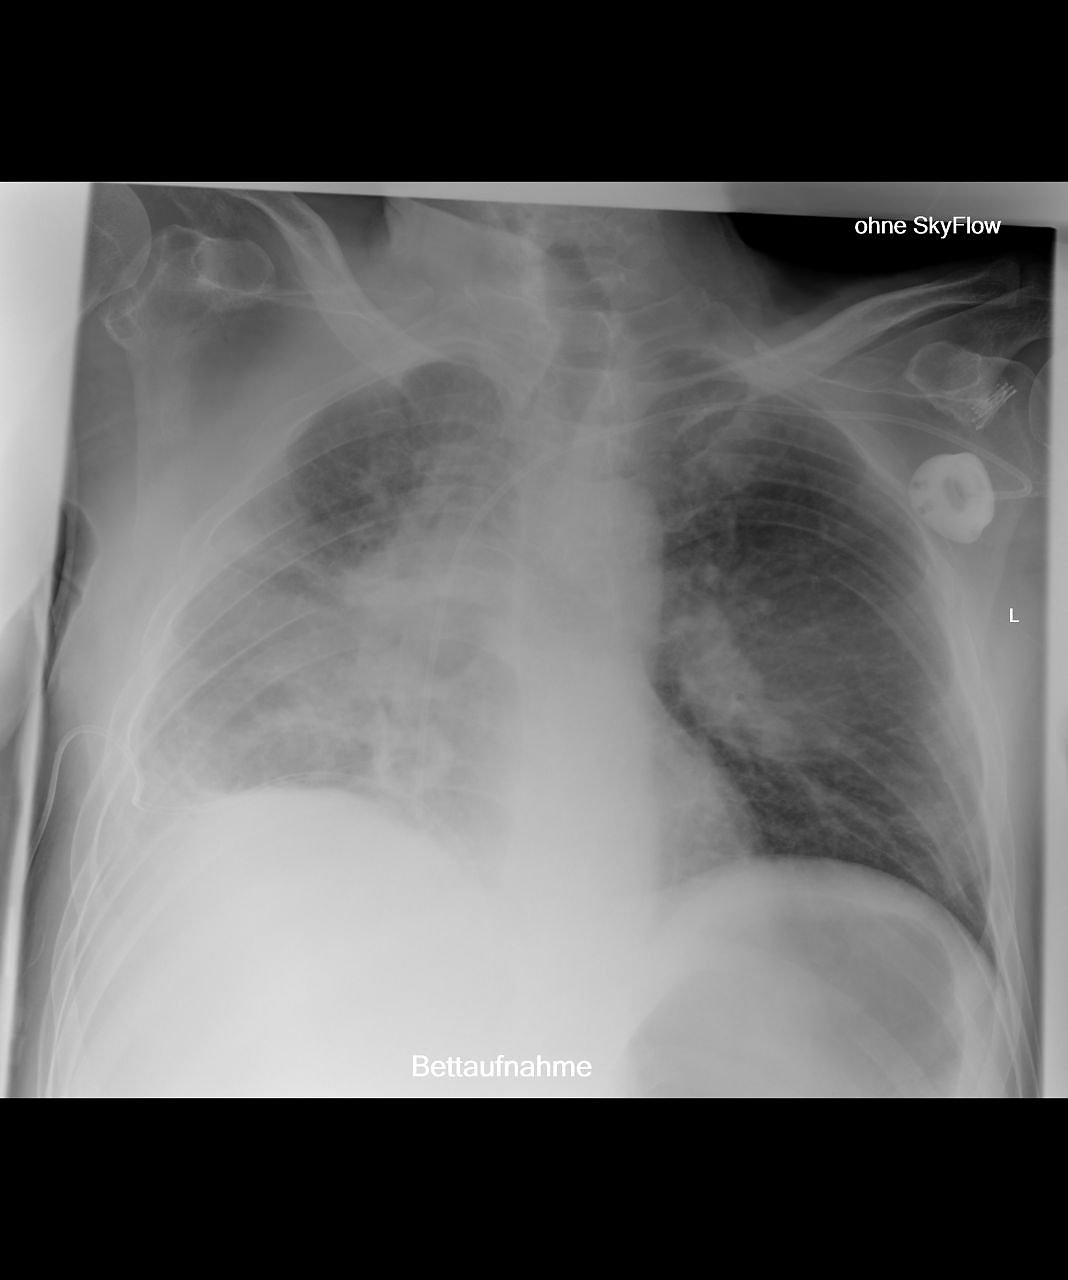

Außerdem ermöglicht die neue Röntgeneinheit die Anfertigung von Ganzbein- und Ganzwirbelsäulenaufnahmen direkt digital mit nachfolgender elektronischer fehlerfreier und versatzfreier Zusammenfügung der Bilddatensätze. Diese Ganzbein- und Ganzwirbelsäulenaufnahmen sind für die Planung endoprothetischer Versorgungen wesentlich. Darüber hinaus sind sie von großem Nutzen in der Therapieabschätzung bei Skoliose oder anderer Fehlstellungen der Wirbelsäule. Auch bezüglich der Bildqualität von im Liegen anzufertigenden Aufnahmen bietet das System wesentliche Vorteile. Häufig werden heutzutage Liegendröntgenaufnahmen mit Verwendung eines Rasters durchgeführt, um die sonst bildqualitativ beeinträchtigende Streustrahlung zu verringern. Die Röntgendosis steigt aber durch diese Rastertechnologie. Alternativ muss man die sonst schlechtere Bildqualität bei Liegendaufnahmen in Kauf nehmen, was die Befundung beeinflussen kann. Nach unserer Kenntnis erstmalig in Thüringen verfügbar, ist nun für diese schwerkranken Patienten (die deshalb nur im Liegen geröntgt werden können) das sogenannte Sky Flow Processing”, erklärt der Chefarzt.

Hierbei wird ein Algorithmus zur Nachverarbeitung der Bilddatensätze angewandt, der streustrahlungsbedingte Effekte des Röntgenbildes automatisch erkennt und durch einen zusätzlichen nachverarbeitenden Filter korrigiert. Die Folge ist eine deutlich verbesserte Bild- und damit verbunden Befundungsqualität, sodass nach bisherigen Studien die Bildqualität ohne Raster mit Sky Slow Technologie der Bildqualität mit Raster entspricht. Auch hierfür ist das radiologische Institut des Südharz Klinikums wiederum Referenzzentrum. Erste interessierte Radiologen haben bereits einen Besuchstermin am Südharz Klinikum vereinbart, um diese neue Nachverarbeitungsoption in praktischer Anwendung zu sehen.